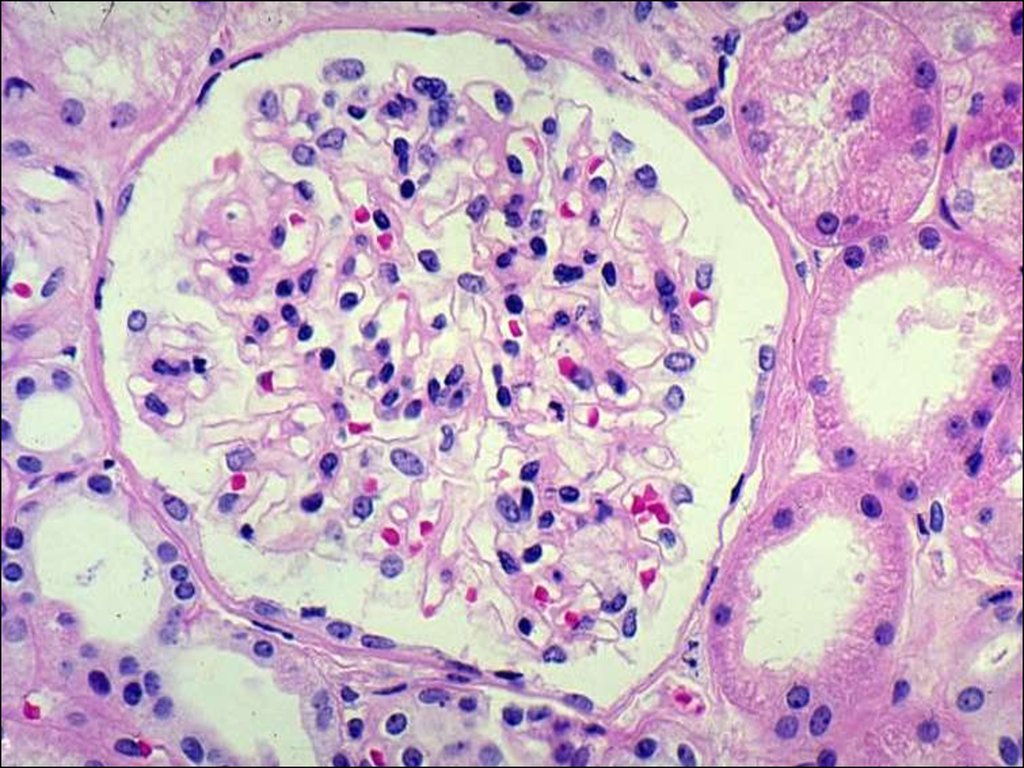

Симптомы подострого гломерулонефрита: фото и описание

Раздел: Визуальный дайджест